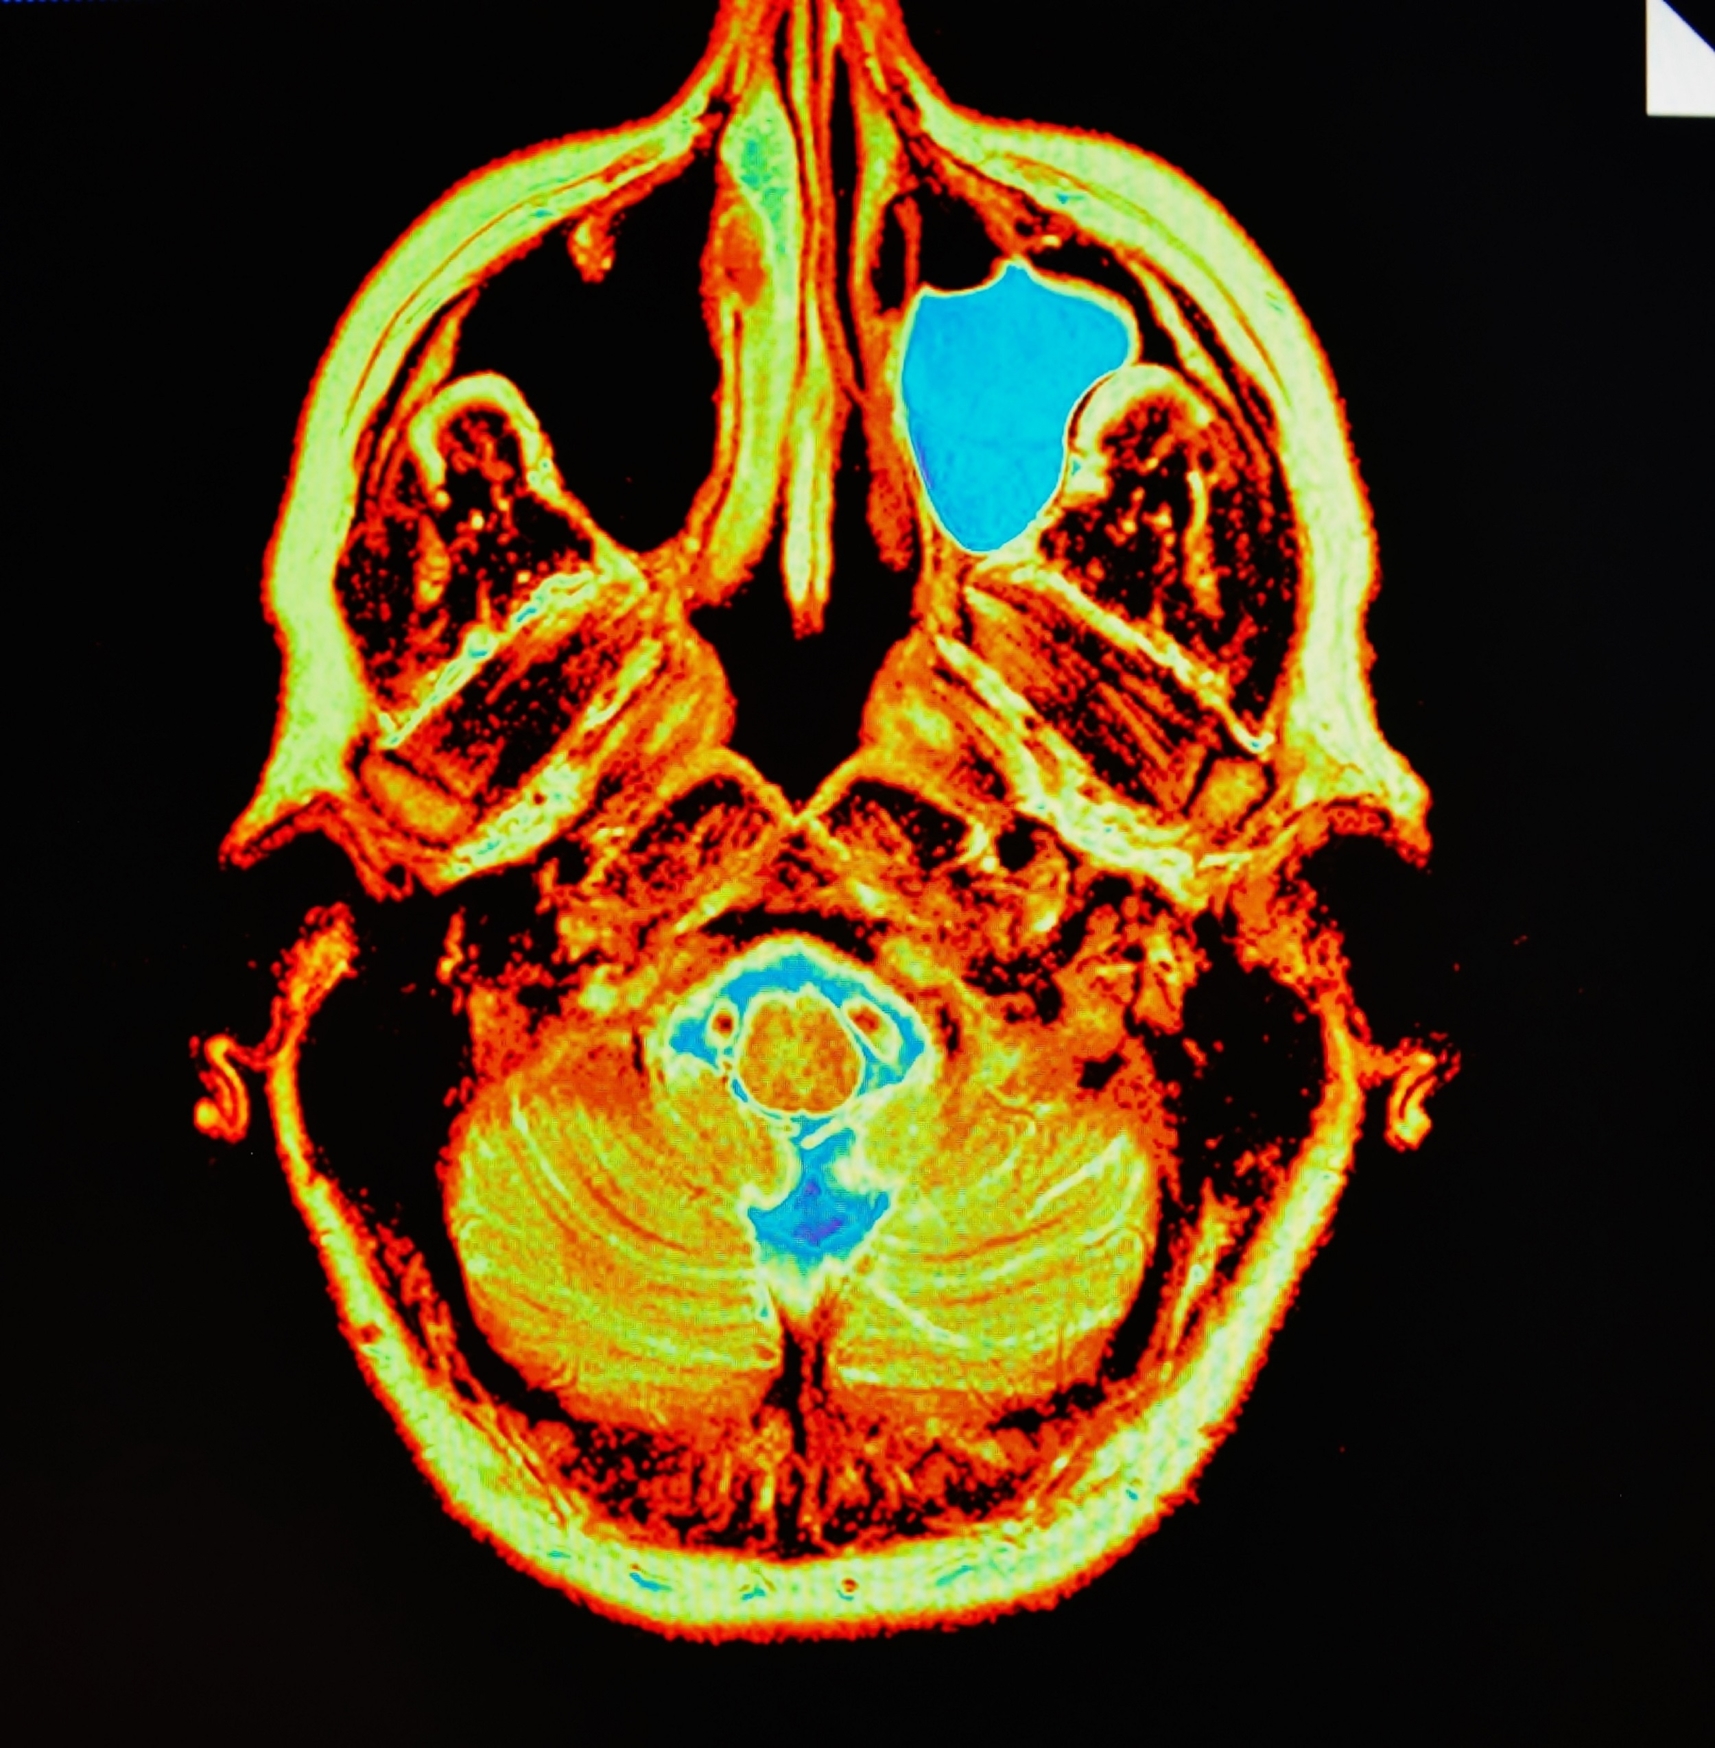

3. Meningoencephalitis

Meningoencephalitis, as the name suggests, is an infection affecting both the brain (encephalitis) and meninges (meningitis). Both present signs of inflammation and the main symptom of meningoencephalitis is swelling of the brain tissue and meninges, which is a protective barrier of the brain and spinal cord. It is usually caused by a viral infection, and a fairly common cause of mumps, but only in rare cases is it serious enough to cause death or neurological complications.